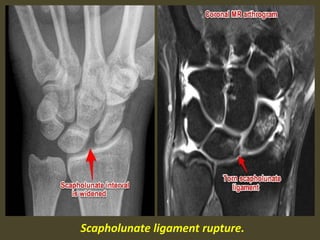

Scapholunate dissociation. Note the widened scapholunate space (“Terry Thomas”

sign) and the foreshortened scaphoid with a “scaphoid ring” sign (arrows).

Adjacent is British comedian Terry Thomas and his famous teeth.

Scapholunate ligament rupture.

Scapho - lunate ligament tear